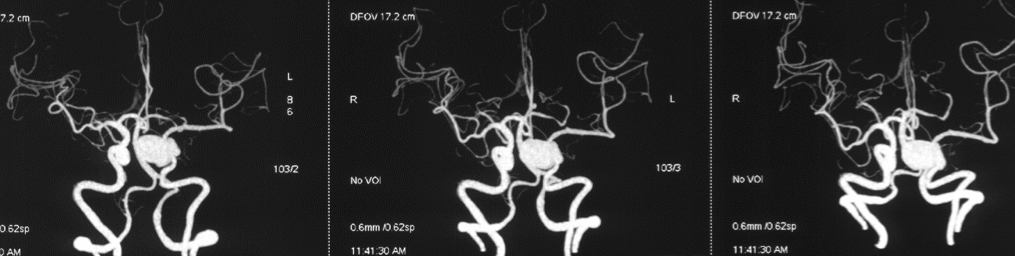

患者取平卧位,全麻满意后,留取尿管通畅,术区常规消毒铺巾,右股动脉行Seldinger穿刺,置入6F动脉鞘,超滑泥鳅导丝携带5FMPA1行脑动脉造影,见左侧海绵窦段巨大动脉瘤,眼动脉段血管异常扩张,左侧A1未见显影。更换8F动脉鞘,超滑泥鳅导丝、5F MPA1、8F Envoy同轴送入左侧颈内动脉,撤出MPA1及导丝,超滑泥鳅导丝携带5F Navien送入颈内动脉,管头位于岩水平段。造影见脑血管痉挛,回撤Navien,静脉予以尼膜同泵入,血管痉挛缓解。选择合适工作角度,路图指引下,Synchro14微导丝携带Marksman支架管送入颈内动脉末端,微导丝头端进入M4,尝试送入微导管仍无法前进,于动脉瘤处反复疝入动脉瘤体内。更换Transcend微导丝送入远端大脑中动脉M2,将支架管送入M1末端,管头位置满意后撤出微导丝,连接高压肝素水持续滴注。选择工作角度,沿支架管送入PED-4.75-35一枚,于大脑中动脉保持支架头端稳定,回撤支架管露出支架头端,缓慢回撤至眼动脉段,保持支架管稳定,推送支架推送杆,动脉瘤瘤颈处适当增加张力,至近端岩骨段转弯处反复调整张力支架仍无法完全贴壁,遂先行原位释放近端,见贴壁良好。保持推送杆稳定,跟入Marksman支架管,支架管经过岩骨段转弯时可见支架展开程度较前改善。回收支架推送杆,沿微导管送入大C塑形后Synchro14微导丝,结合支架管弓背按摩支架,见支架贴壁明显改善。

XperCT提示支架贴壁良好,造影见载瘤动脉通畅,动脉瘤内血流迟滞。遂结束手术,撤出各级导管系统,穿刺点封堵止血满意后加压包扎固定良好。患者麻醉苏醒后平车送回病房,术后给予监护、吸氧、抗血小板聚集、抗血管痉挛等对症治疗,嘱患者穿刺侧肢体绝对制动6小时,卧床24小时,术后注意患者意识、瞳孔、肢体活动等。

造影见左侧颈内动脉海绵窦段巨大动脉瘤,瘤体远端海绵窦水平段血管狭窄,眼动脉段血管扩张,左侧A1段缺如

术后XperCT提示支架贴壁良好